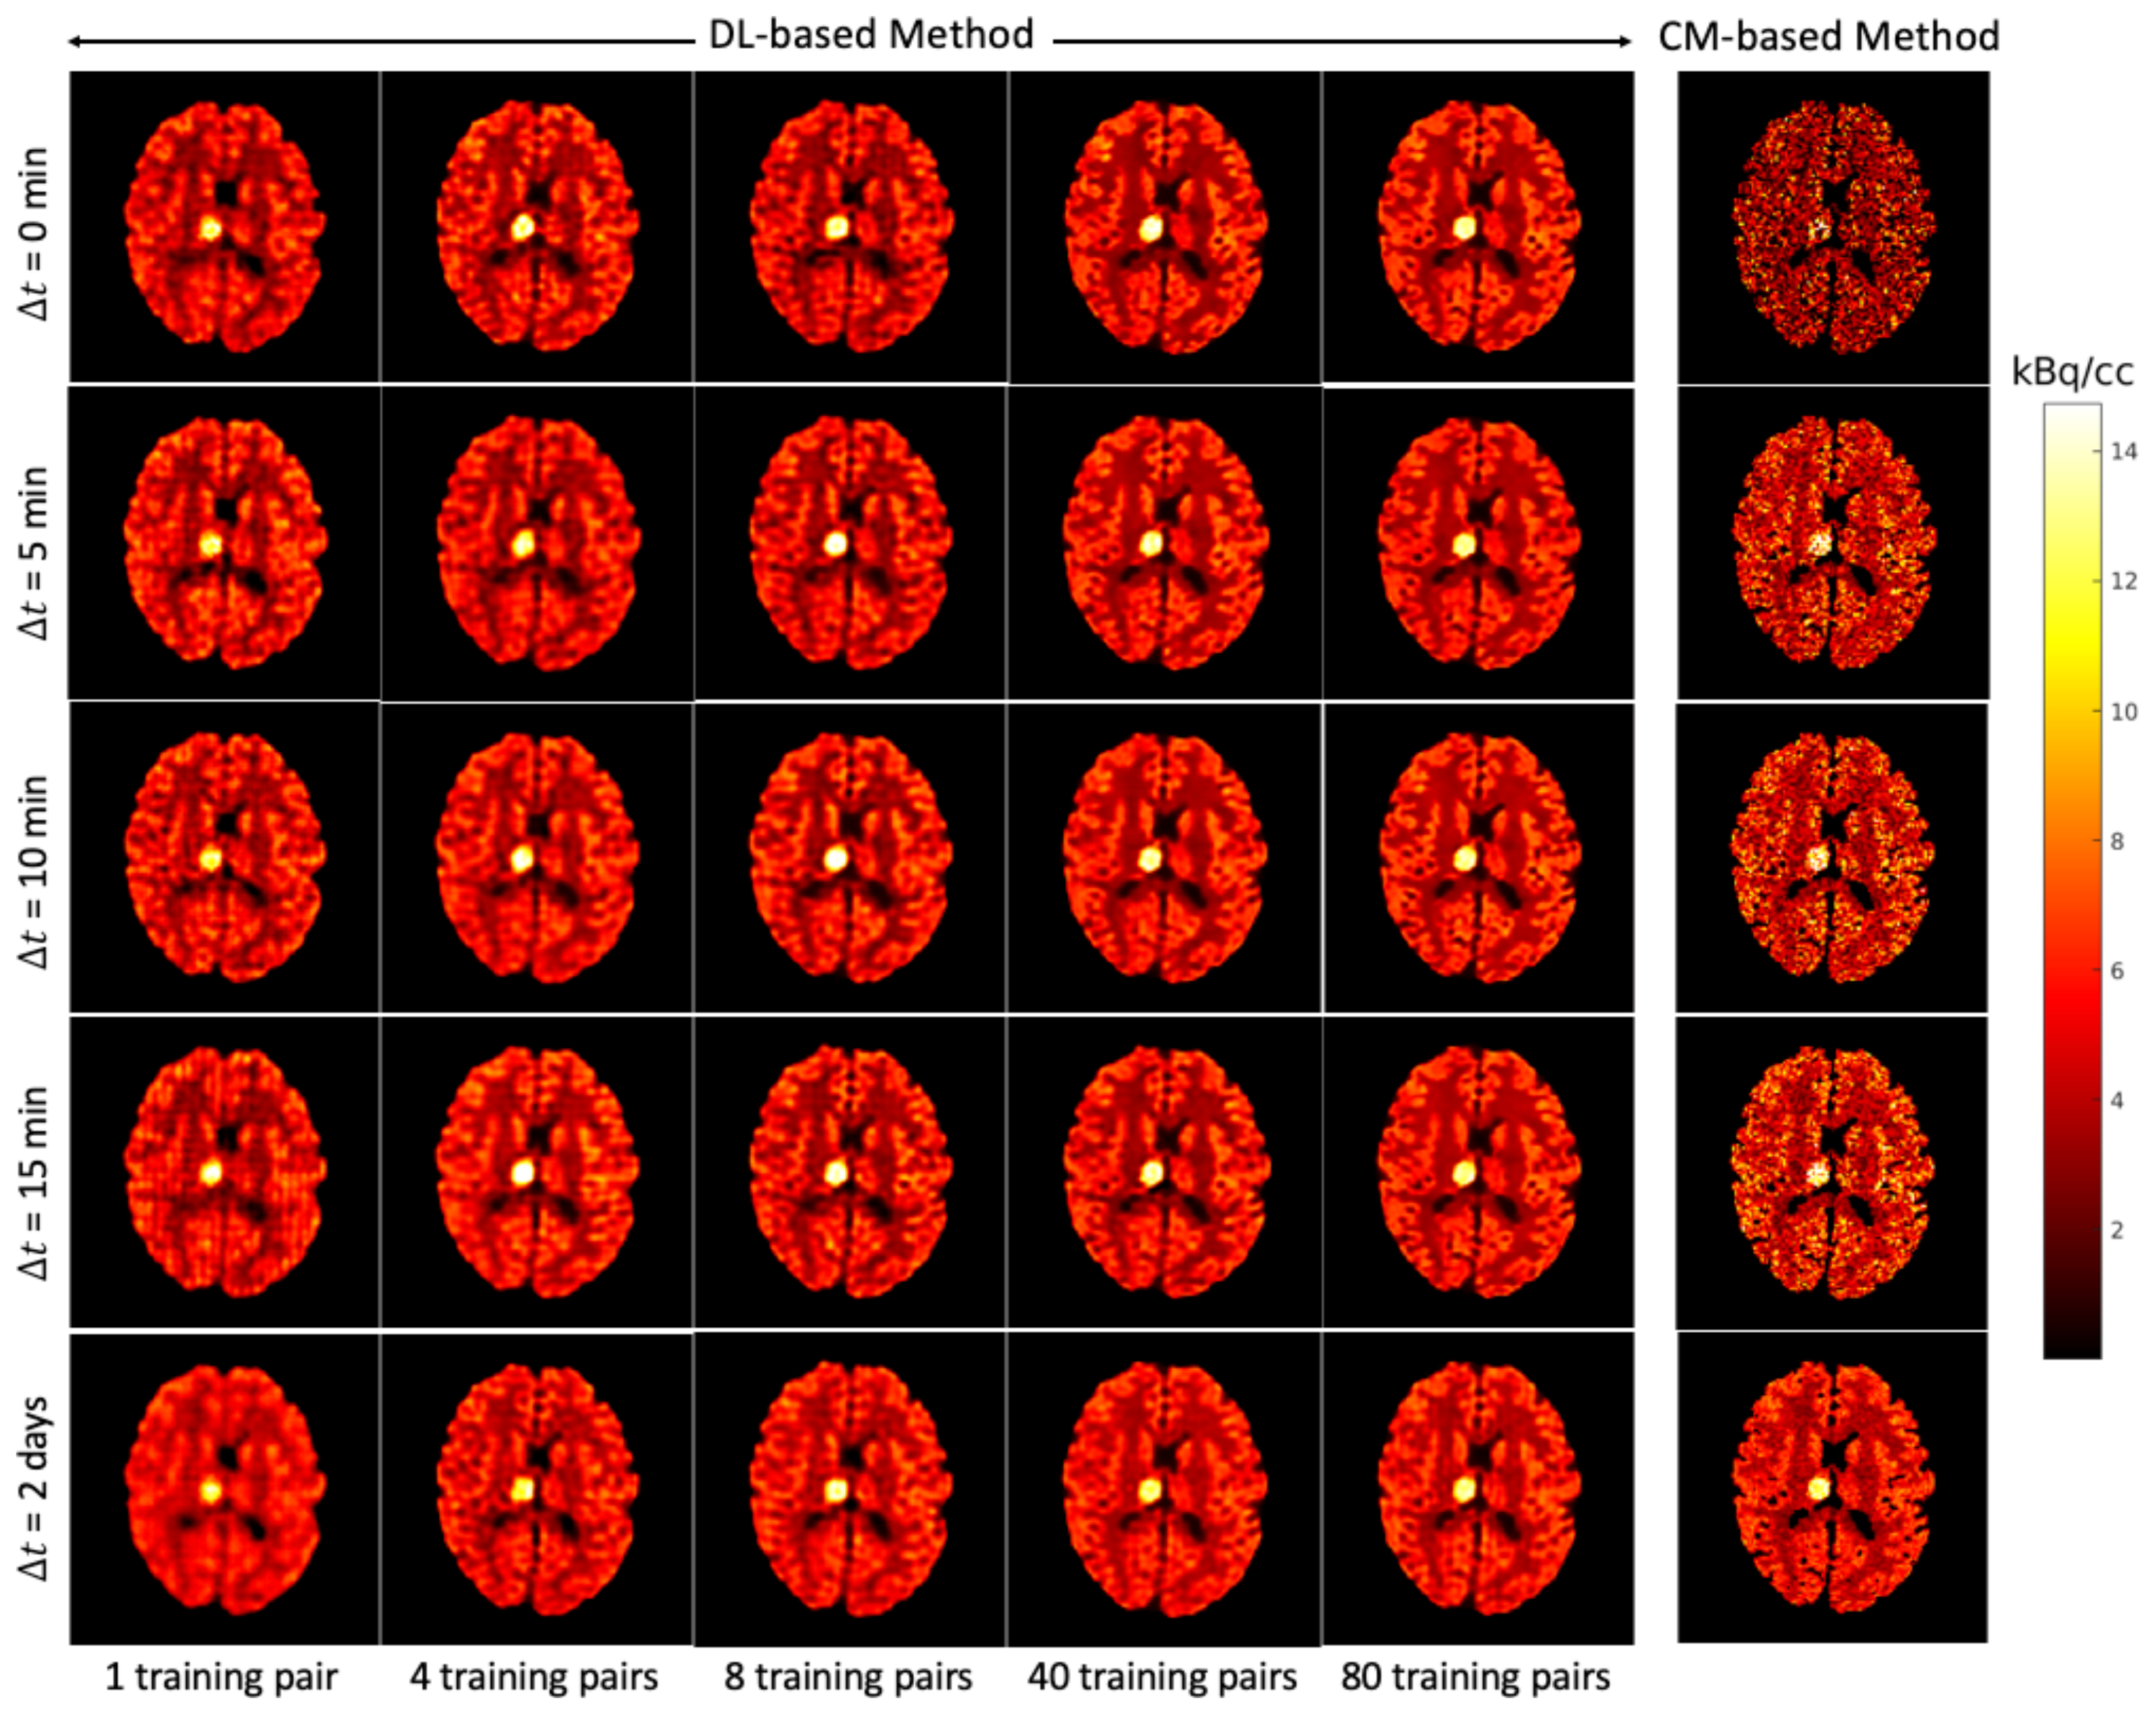

Figure 7 shows for each that the average NRMSE decreases and that a smaller SD is obtained in the test set as the number of training pairs increases from 1 to 80. This is consistent with the visual impression of the separations obtained by the DL-based method, as shown in Figure 8 and Figure 9. The first to fifth columns display the separated static single-tracer images (activity distributions) based on different numbers of training pairs (for plotting only, we limit the colour scale of the figures to fall within the same range as the reference images in Figure 6b for and Figure 6e for , respectively). Although all cases successfully recover the separated images, using more training pairs results in higher separation performance in terms of recovering the tumour regions, shapes and low contrast of the white and grey matter for . Figure 10a,c also suggest that the more training pairs used, the better the average NRMSE, which is in line with the results shown in Figure 7. With 80 training pairs, the DL-based method achieved average NRMSE values for FDG and MET of ∼15% and ∼12%, respectively, for the test set across all (see the magenta lines in Figure 10a,c).

Figure 8.

Brain phantom (whole brain region): the static images recovered using the DL-based method (Columns 1 to 5) and the CM-based method (Column 6).

A test example of the separated images using the CM-based method is shown in the last column of Figure 8 (FDG) and Figure 9 (MET) for different . Compared to the results obtained from the DL-based method, the separated images using the CM-based method are much noisier because the model fitting (4) may fall into local minima even when the noise level is low. Although several strategies, such as using differing initial values or an exhaustive search algorithm [22], have been suggested to reduce local minima, their use in clinical practice is challenging because of their high computational cost.

4.3. DL-Based Method and CM-Based Method Comparison

The separation results between the DL-based method and CM-based method applied to the reconstructed dynamic dual-tracer noisy MLEM images were compared. For = 0, 5, 10 and 15 min, Figure 8 and Figure 9 show that in terms of visual assessment the CM-based method produces much nosier separated images than the DL-based method. This observation is consistent with better average NRMSE values of the DL-based separation results as illustrated in Figure 10. When using only 1 training pair, the DL-based method achieved high average NRMSE values across all (∼25% for FDG and ∼22% for MET). However, it nevertheless produces better average NRMSE values for = 0, 5, 10 and 15 min when compared to the separation results using the CM-based method. In fact, there are TACs contained in 1 training pair, one for each voxel; hence, in this instance, the proposed network was trained using TACs. Note that the DL-based method utilises both spatial and temporal information of the TACs from all voxels, but the CM-based method was implemented voxel by voxel, meaning only temporal information of one TAC was considered at each time. Therefore, for = 0, 5, 10 and 15 min, the DL-based method with 1 training pair yields better separation performance. When = 2 days, the CM-based method, in contrast to the DL-based method with 80 training pairs, achieved lower average NRMSE values for both FDG and MET. We believe this is the result of not enough training data which includes the case of = 2 days.